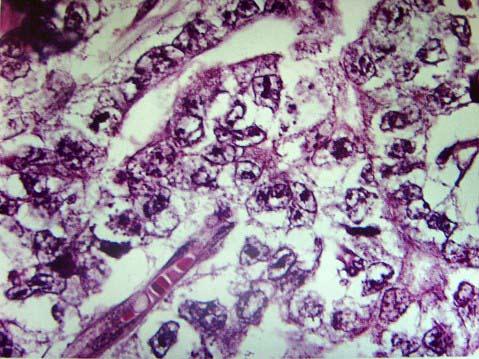

问题 男性,35岁,睾丸无痛性肿块,大小3cm×3cm×4cm,肿块境界不清,切面灰白、灰红,局灶出血、坏死(如图),显微镜下如图,应诊断为 ( )

选项 A.精原细胞瘤 B.卵黄囊瘤 C.绒毛膜上皮癌 D.胚胎性癌 E.以上都不是

答案 D